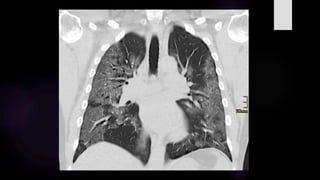

El COVID-19 típicamente induce una neumonía bilateral

difusa intersticial con lesiones en distribución asimétrica y

parcheada que afecta principalmente a la periferia pulmonar.

El método de imagen ampliamente utilizado para la valoración de

COVID-19 es la TC de tórax, y aunque los hallazgos van cambiando con

con la evolución de la enfermedad; la identificación de los signos

radiológicos dependen del desempeño del observador.